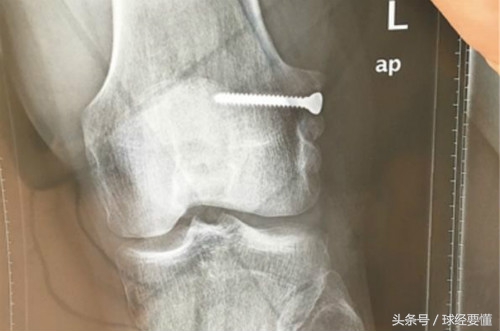

任鹏是来自足球城大连的球员,2013年呼和浩特东进加盟深足。在任鹏17岁那年,因为左膝韧带撕裂,大连铁路医院医生取了一段他的肌腱,用钢钉作为支点,固定在骨头里促进生长,才让他没有离开足球。

13年后,任鹏近日在深圳一家医院,取出了那颗陪伴他13年的钢钉,“17岁的时候医生说我基本可以告别足球了,当时我不愿放弃,命运也不能让我跪地求饶。很幸运我熬过来了,现在我决定把钢钉拿出来,也是为了继续追逐自己的梦想,我相信我还能踢。”

之所以要取出这颗钢钉,是因为前段时间任鹏参加一场预备队比赛,撞伤了左腿膝盖,需要进行核磁共振检查。然而,由于这颗钢钉在骨头里,核磁共振就没法进行了。经过医院诊治,任鹏决定先把钢钉取出来,以便于膝盖的进一步治疗。

在医院做了两个多小时手术,把钢钉取出来的任鹏,还需要回家静养1、2个月,再确定左膝盖伤势并进行相关治疗。作为一个30岁的老将,任鹏还想延续自己的职业足球梦,就要付出比常人更多的努力和代价。